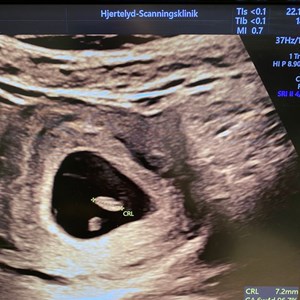

Det lille spirende liv uge 8 💓 Det lille fine fosteranlæg her er bare 17,5 mm lang. Det ...

TIDLIG TERMIN-SCANNING 👀🫶🏼🫧 Skal du/I til tidlig scanning i graviditetens første tri...